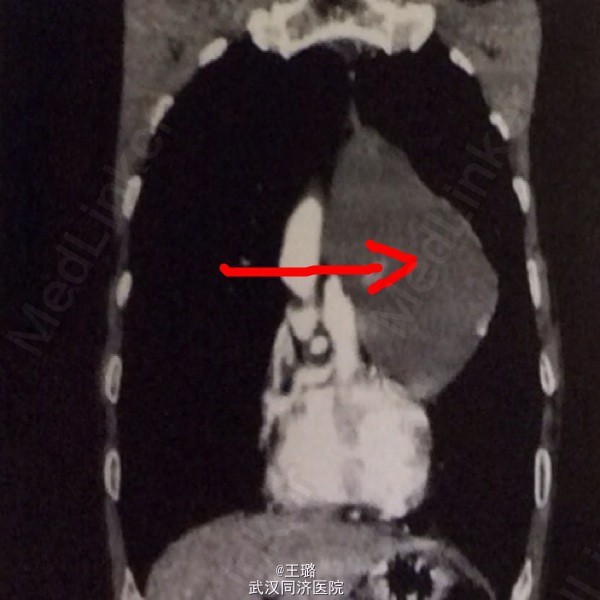

患者,男,63岁,胸闷一星期加重两天入院。体格检查:两肺呼吸音稍粗,未闻及干湿啰音。实验室检查:中性粒细胞增高,淋巴细胞降低,其余无异常。CT示:前纵隔左侧出现类圆形囊性病灶,边缘可见实性结节。MPR示:囊性占位内可见细条状分隔,囊肿与周围结构界限清晰。遂给予手术切除,术后病检示:多房性胸腺囊肿。胸腺囊肿为纵隔良性肿瘤,较少见,若囊肿破溃穿入心包可引起心包填塞。